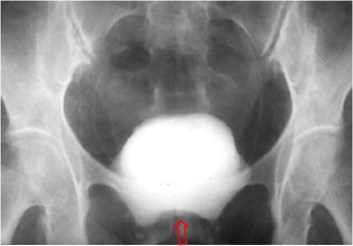

SIGNO DE LA PRÓSTATA FEMENINA

Signo visible en la urografía intravenosa o la cistografía de una mujer, correspondiente a una impresión en el suelo vesical similar a la impronta prostática del varón. Puede ser producida por lesiones neoplásicas o inflamatorias de la zona.

La imagen de TC corresponde a la misma paciente de la urografía, que presenta un tumor de cuello uterino -flechas negras- que infiltra la vejiga. Se trataba de un adenocarcinoma mucosecretor. La imagen recuerda a la impronta prostática en el TC.

Otro ejemplo de este signo en una paciente con hipertrofia del músculo elevador del ano.